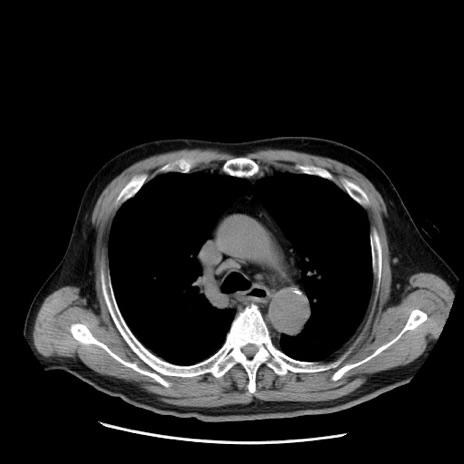

症例20(横断像)

【症例】 60歳代男性

【主訴】 腹部膨満、嘔吐

【現病歴】5日前頃より倦怠感を認め食事量減少し4日前の朝嘔吐、食事摂取困難となった。 3日前近医受診し点滴施行され整腸剤などを処方された。 当日他院を受診し、腹部膨満著明、炎症反応の上昇(CRP10.8、WBC11200)あり、紹介受診となる。

【身体所見】 意識JCS1 受け答えがはっきりしないBP 111/57mHg、 P 67bpm、、BT35.2°C、SpO2 97%(RA)、 腹部:膨隆、打診で鼓音あり、全体的に圧痛有り、腸蠕動音(-)、反跳痛ははっきりせず。

【データ】WBC 11400、CRP 14.20